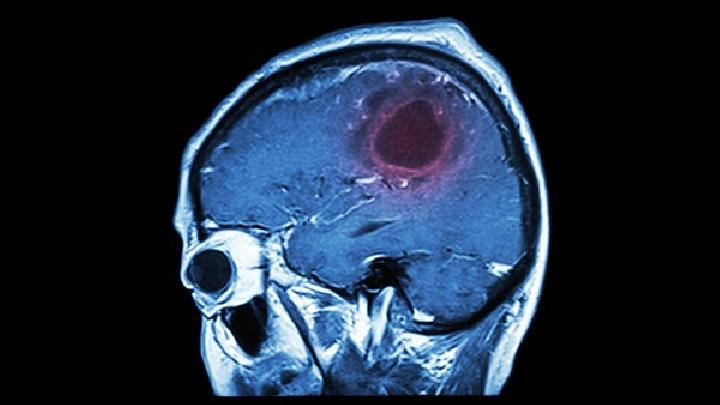

二、脑功能的损害:小儿脑瘫对患者的危害很大,专家说,小儿脑瘫每发作一次,脑细胞损害一次,长期的小儿脑瘫反复发作,患者会智能下降,最后逐渐丧失工作能力,甚至生活能力。